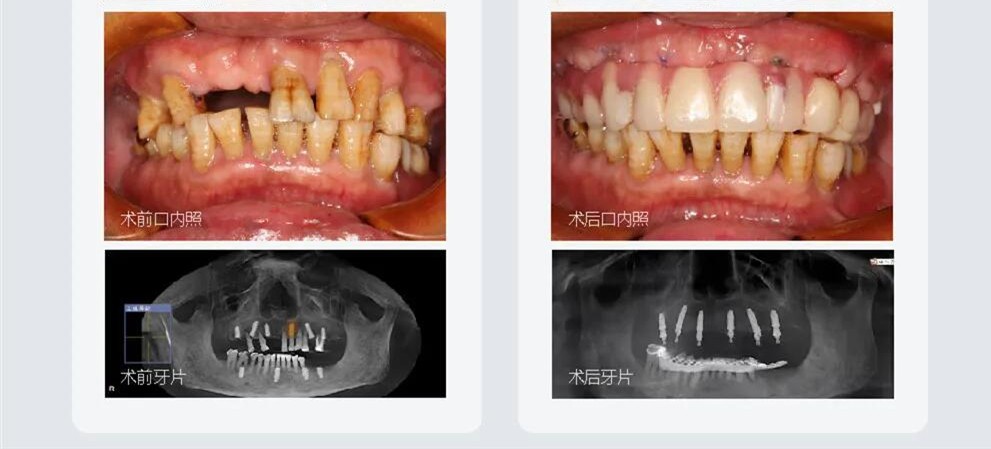

2、精通各種疑難雜癥種植技術(shù),即刻種植、3D數(shù)字化導板種植,全口/半口、無牙頜種植技術(shù)等。